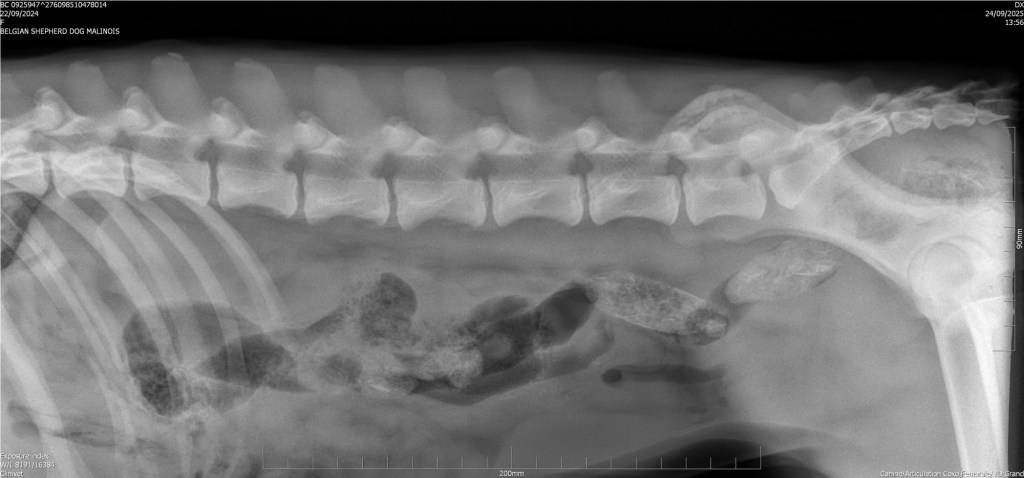

Back clear